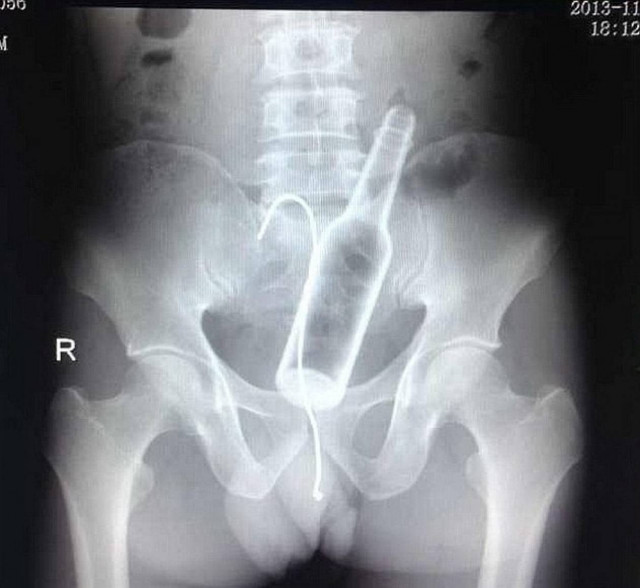

ΣΟΚ: Έμειναν άναυδοι όταν βρήκαν ένα μπουκάλι και ένα αγκίστρι στον...

ΚΟΣΜΟΣ · 10.01.2014 - 09:08

Ρεζίλι των σκυλιών έγινε ένας άντρας στο νοσοκομείο Φουτζού της επαρχίας Φουτζιάν στην Κίνα, όταν πήγε για να κάνει ακτινογραφίες και ανακάλυψαν οι γιατροί ότι…